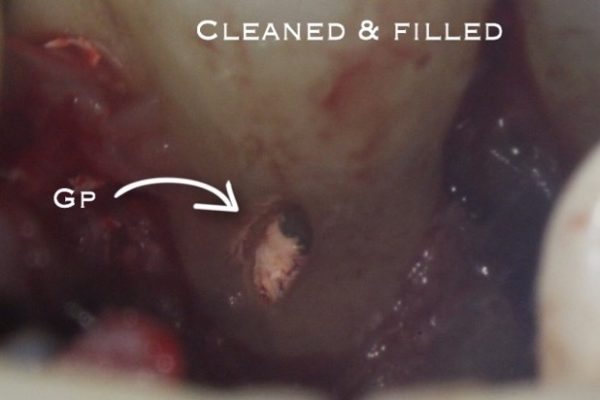

A full thickness muco-periosteal flap is raised and ECR lesion is visualised.

We remove the granulation tissue with a curette.

Then we use burs or ultrasonics to conservatively clean the surrounding tooth. The granulation tissue must also be removed from the surrounding bone.

We can then restore the cavity with plastic filling (Figures 7 and 8).

Various filling materials can be used; composite (Figure 9), GIC, RMGIC or biodentine.

The material choice depends on the degree of moisture control achievable, aesthetic considerations and ability for PDL reattachment.